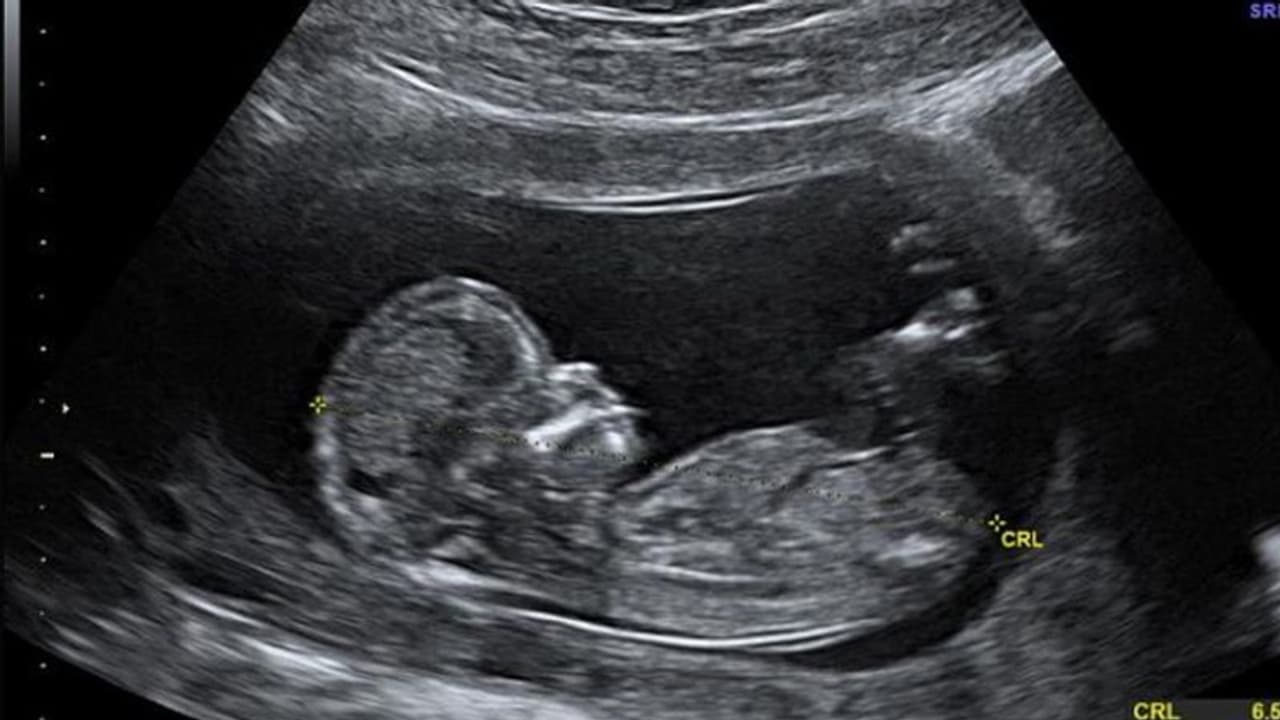

ಮೈಕ್ರೋಪ್ಲಾಸ್ಟಿಕ್ ಅಂದರೆ ಪ್ಲಾಸ್ಟಿಕ್ನ 5 ಮಿ.ಮೀ.ಗಿಂತ ಸಣ್ಣ ಚೂರುಗಳು. ಹೊಕ್ಕುಳಬಳ್ಳಿಯು ಭ್ರೂಣಕ್ಕೆ ಆಹಾರ, ರಕ್ತ ಹಾಗೂ ಆಮ್ಲಜನಕ ಒದಗಿಸುವ ಮತ್ತು ಗರ್ಭಕೋಶದಿಂದ ತ್ಯಾಜ್ಯವನ್ನು ಹೊರಹಾಕುವ ಕೆಲಸ ಮಾಡುತ್ತದೆ. ಇಲ್ಲಿ ಮೈಕ್ರೋಪ್ಲಾಸ್ಟಿಕ್ ಪತ್ತೆಯಾಗಿದೆ ಅಂದರೆ ಅದು ಮಗುವಿನ ದೇಹಕ್ಕೂ ಹೋಗಿರುತ್ತದೆ. ಅಂದರೆ ಈಗ ಮಕ್ಕಳು ಸಂಪೂರ್ಣವಾಗಿ ಸಾವಯವ ಪದಾರ್ಥಗಳನ್ನು ಮಾತ್ರ ದೇಹದಲ್ಲಿಟ್ಟುಕೊಂಡು ಹುಟ್ಟುತ್ತಿಲ್ಲ, ಬದಲಿಗೆ ಅಸಾವಯವ ವಸ್ತುಗಳನ್ನೂ ದೇಹದಲ್ಲಿಟ್ಟುಕೊಂಡು ಹುಟ್ಟುತ್ತಿವೆ ಎಂದು ತಜ್ಞರು ಅಭಿಪ್ರಾಯಪಟ್ಟಿದ್ದಾರೆ.

ಇಟಲಿಯಲ್ಲಿ ಹೊಕ್ಕುಳ ಬಳ್ಳಿಯನ್ನು ದಾನ ಮಾಡಲು ಮುಂದಾದ ಆರು ಮಹಿಳೆಯರ ಪೈಕಿ ನಾಲ್ಕು ಮಹಿಳೆಯರ ಹೊಕ್ಕುಳ ಬಳ್ಳಿಯಲ್ಲಿ ಮೈಕ್ರೋಪ್ಲಾಸ್ಟಿಕ್ ಪತ್ತೆಯಾಗಿದೆ. ಹೊಕ್ಕುಳ ಬಳ್ಳಿಗೆ ಪ್ಲಾಸ್ಟಿಕ್ ಹೋಗಬೇಕು ಅಂದರೆ ಅದು ಮಹಿಳೆಯ ರಕ್ತದಲ್ಲೇ ಸೇರಿರಬೇಕು. ಕೇವಲ ಹೊಟ್ಟೆಗೆ ಪ್ಲಾಸ್ಟಿಕ್ ಹೋಗಿದ್ದರೆ ಅದು ಮಲದಲ್ಲಿ ಹೊರಹೋಗುತ್ತದೆ. ಹೀಗಾಗಿ ರಕ್ತದ ಪ್ರವಾಹಕ್ಕೆ ಮೈಕ್ರೋಪ್ಲಾಸ್ಟಿಕ್ ಹೇಗೆ ಸೇರಿಕೊಂಡಿತು ಎಂಬ ಬಗ್ಗೆ ಹೆಚ್ಚಿನ ಅಧ್ಯಯನ ನಡೆಯಬೇಕಿದೆ. ಹೊಕ್ಕುಳ ಬಳ್ಳಿ ಅಥವಾ ಮಗುವಿನ ದೇಹದಲ್ಲಿ ಮೈಕ್ರೋಪ್ಲಾಸ್ಟಿಕ್ ಸೇರಿಕೊಂಡರೆ ಮುಂದೆ ಅದು ನಾನಾ ರೀತಿಯ ಅನಾರೋಗ್ಯದ ಸಮಸ್ಯೆಗಳಿಗೆ ಕಾರಣವಾಗಬಹುದು ಎಂದು ವಿಜ್ಞಾನಿಗಳು ಆತಂಕ ವ್ಯಕ್ತಪಡಿಸಿದ್ದಾರೆ.